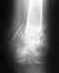

Re: Перелом н/3 обеих костей голени, неправильный остеосинтез

Александр, подскажите пожалуйста - переделать лучше сейчас или можно подождать, скажем, до осени? - боюсь работу потерять, столько "отдыхал"...Через какое время после операции смогу быть на ногах в случае, если операция пройдет удачно? Я слышал, что через короткое время после такой операции начинают нагружать ногу, правильно?

По поводу "сделать изначально" - никаких других вариантов, кроме пластины, изначально не предлагалось (я даже не в курсе был, что можно сделать как-то иначе - теперь вот в курсе...). Боюсь, этого в нашей "деревне" не делают, и нужно смотреть в сторону Питера или Москвы, знать бы ещё, куда конкретно смотреть...